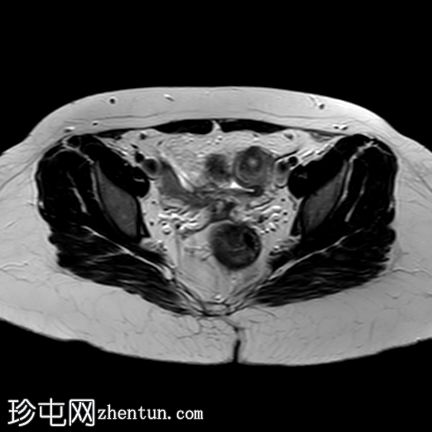

轴位

T2加权像

轴位T2加权像

薄层扫描

盆腔两侧可见两个残角,位于双侧卵巢尾侧。可见一条水平带连接两个残角。左侧残角呈腔状,右侧残角呈非腔状。

可见宫颈阴道发育不全,从两个残角延伸出少量发育不良的宫颈组织带。

双侧卵巢功能正常,可见卵泡。

本病例展示了一种 Mayer-Rokitansky-Küster-Hauser 综合征 (MRKH),其特征为子宫缺失和双侧残角;左侧子宫角呈腔状,右侧子宫角呈非腔状。子宫角位于盆腔两侧,双侧卵巢尾侧,并由一条水平带连接。该病伴有宫颈阴道发育不全。